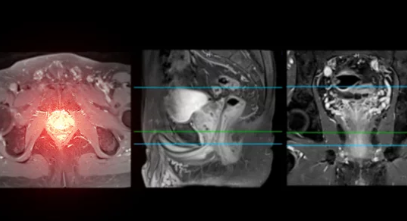

3. 전립선암 진단 방법: 정확한 검진으로 암 발견하기

정기 검진은 전립선암을 조기 발견하는 가장 중요한 수단입니다. 전립선암 검사는 간단하지만, 전립선암의 초기 단계를 효과적으로 진단할 수 있는 방법이 있습니다.

의사가 직접 손가락을 이용하여 전립선의 크기와 형태를 확인하는 방법입니다. 초기 발견을 위해 PSA 검사와 함께 자주 사용됩니다. - 초음파 및 조직 검사

PSA 검사나 직장수지검사에서 이상이 발견되면, 보다 정밀한 초음파 검사나 조직 검사를 통해 확진을 내립니다. 조직 검사는 전립선암 여부와 암의 종류, 진행 단계를 판단하는 데 도움을 줍니다.